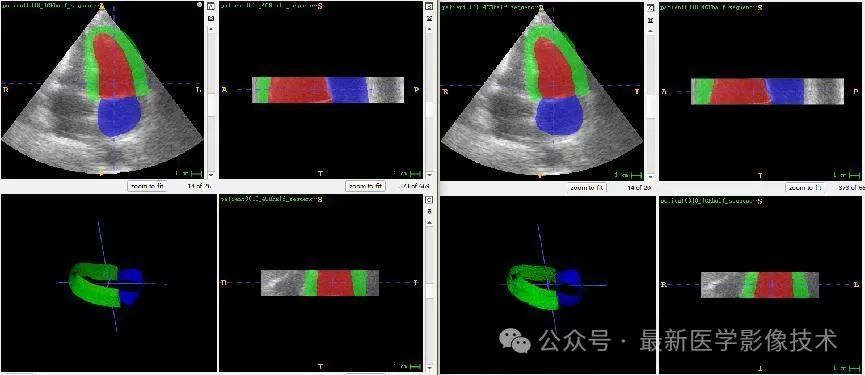

任务二、超声心动图3d结构分割

1、将图像缩放到固定大小512x512x48。图像预处理,再采用均值为0,方差为1的方式进行归一化处理,再将数据分成训练集和验证集,并对训练数据进行数据增强扩增5倍。

2、搭建VNet3d网络,使用AdamW优化器,学习率是0.001,batchsize是1,epoch是300,损失函数采用多类别的dice和交叉熵。

3、训练结果和验证结果

4、验证集部分分割结果

左边是金标准结果,右边是预测结果。